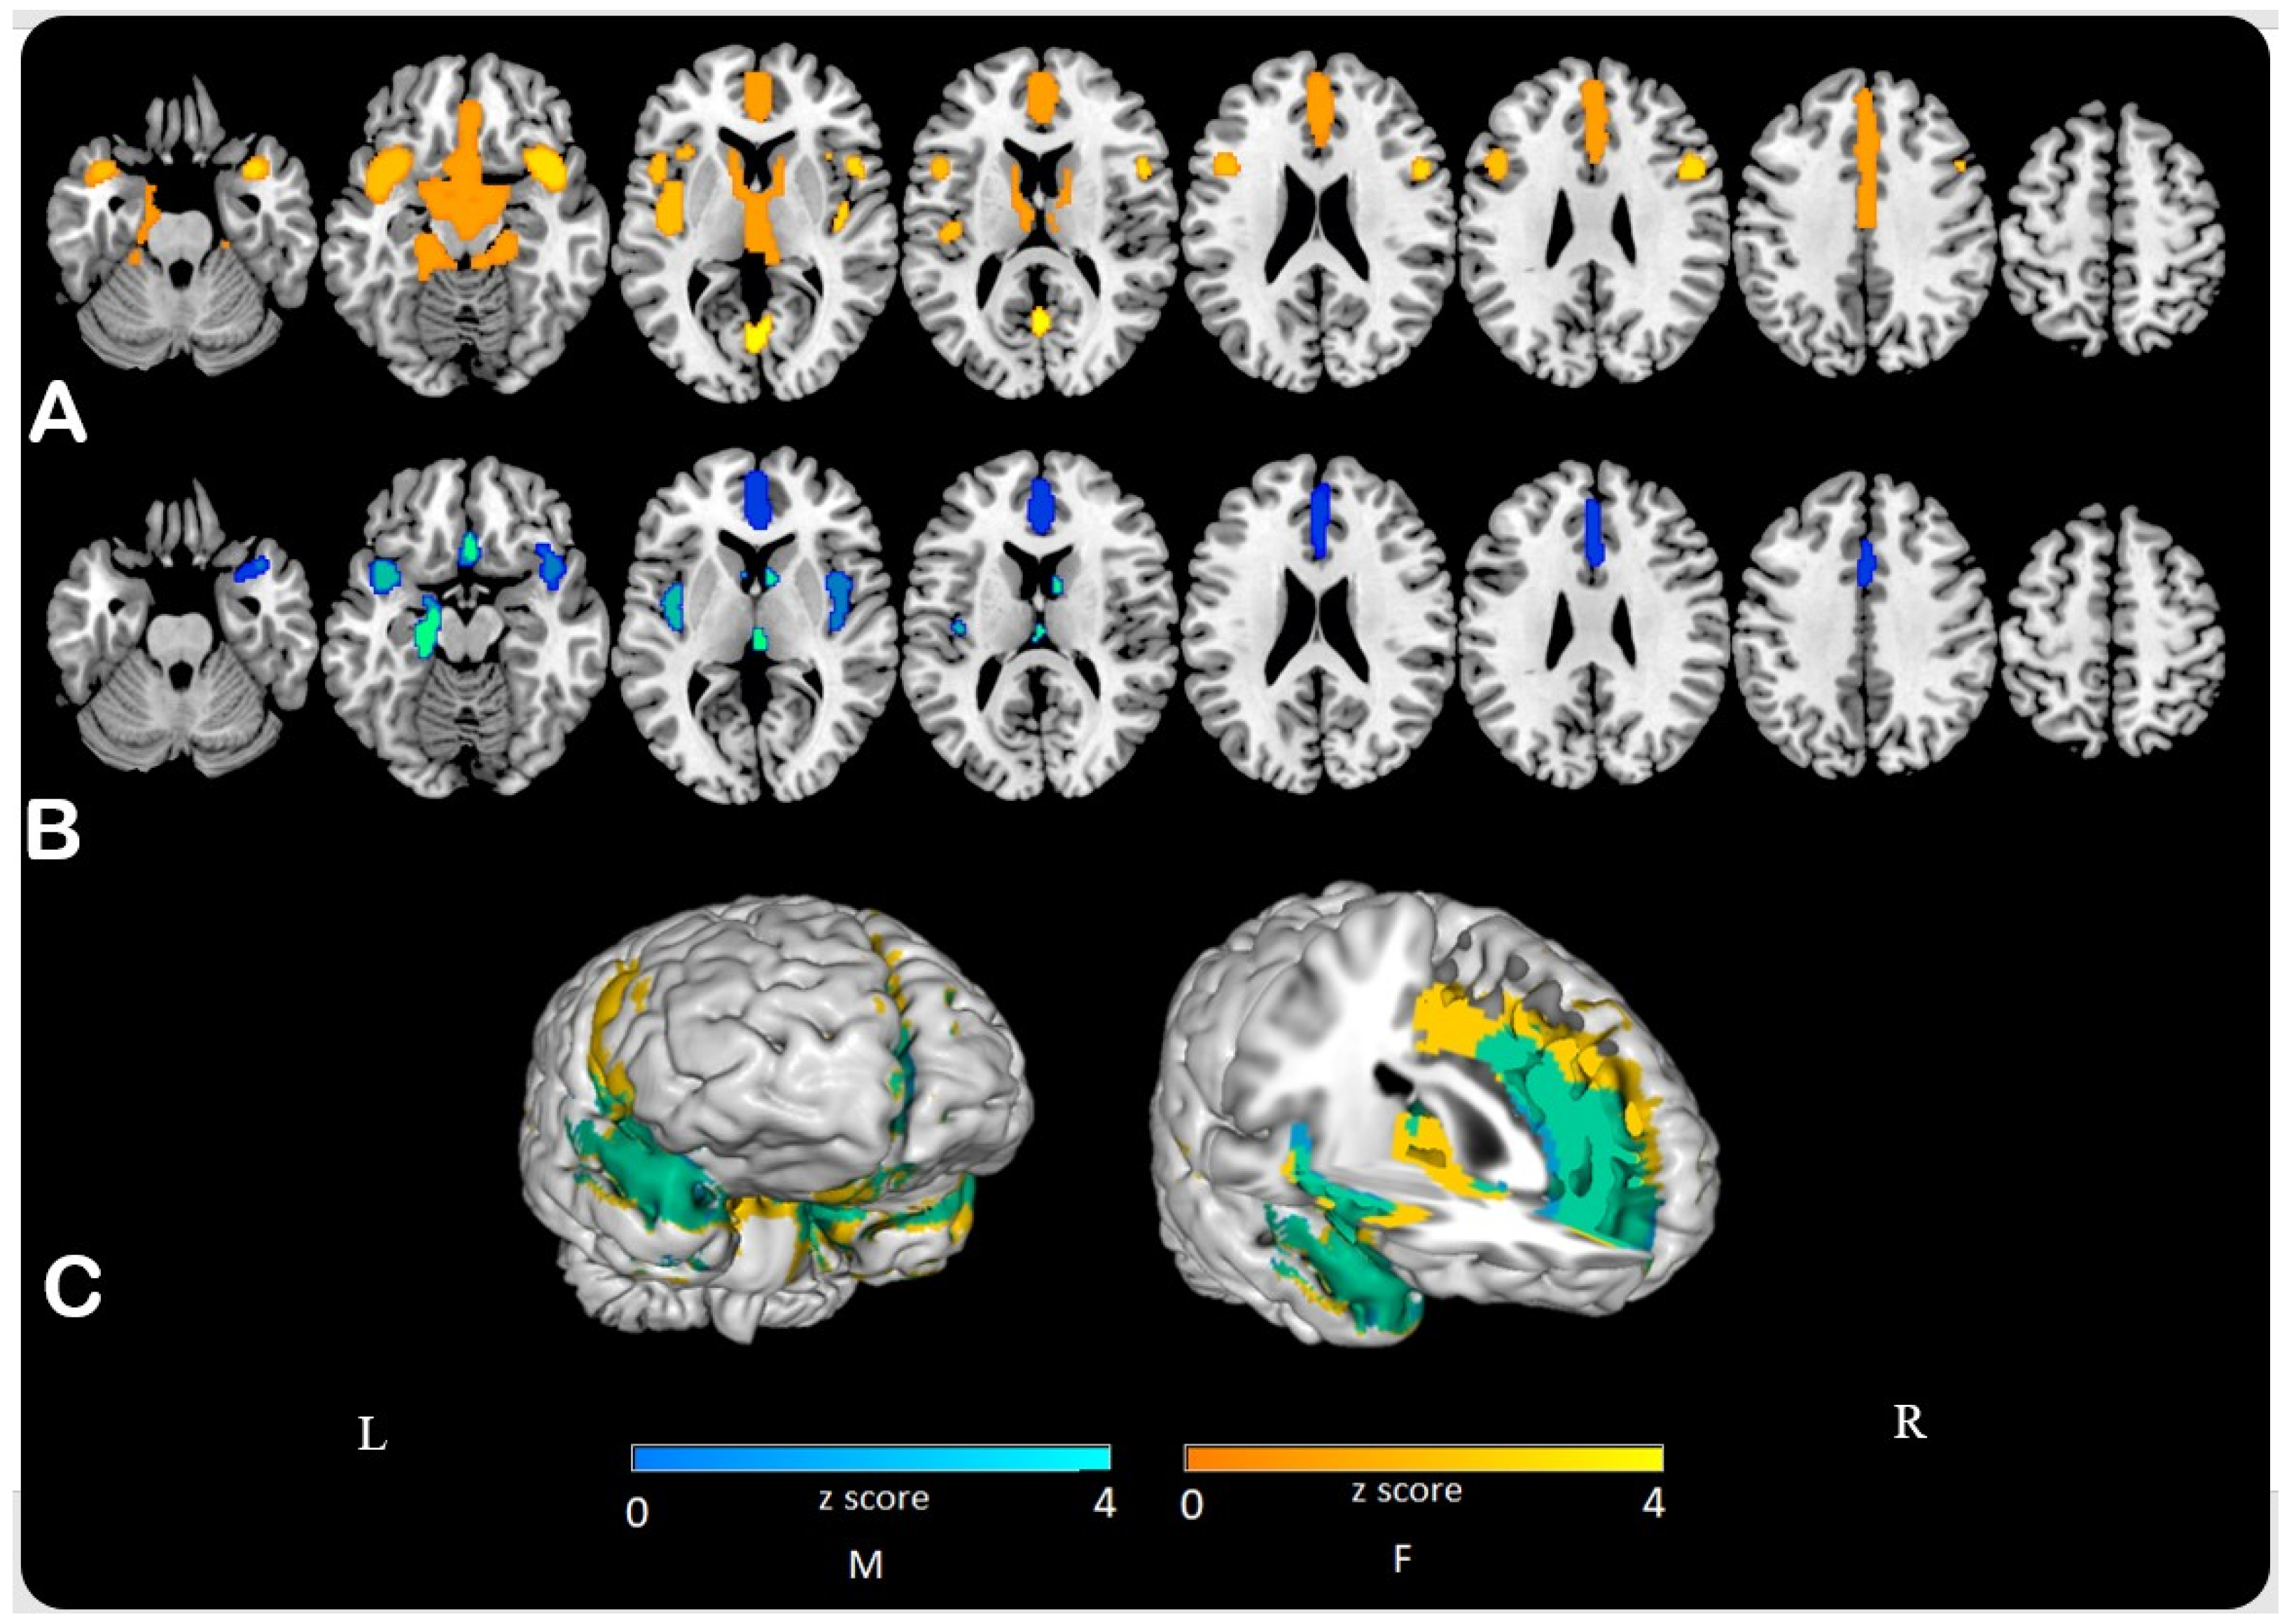

3.1. SPM Analysis